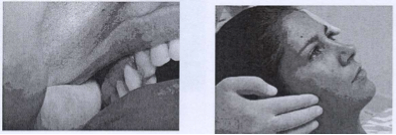

(Test dei rulli di cotone o del Bite idrodinamico a vasi comunicanti).

Rulli di cotone:

Interporre due rulli di cotone fra i denti (o due strisce di neoprene spesse 5-6 mm). Far camminare e deglutire più volte il paziente (bastano 5-6 deglutizioni, una ventina di secondi circa) e verificare le variazioni posturali indotte. Se la postura migliora si può ritenere che la bocca sia un fattore scatenante (sindrome discendente), se peggiora attenzione: potremmo essere di fronte ad una occlusione di compenso di una altra causa (occhi, bacino, arto corto ecc.) (sindrome ascendente). In questi casi è opportuno affiancare la terapia posturale ad una terapia occlusale, magari con bite preconfezionati (mioset).